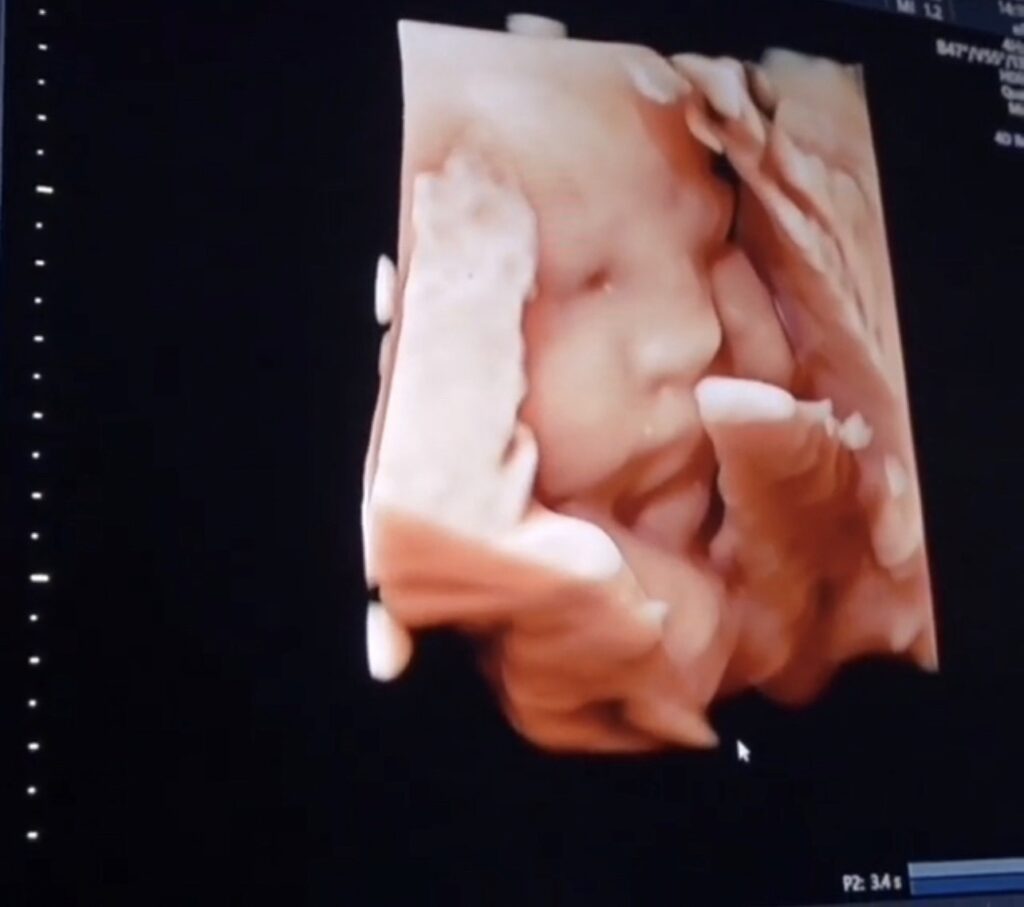

ทำเอาเหล่าคุณแม่หลายๆบ้านที่มีบุตรยากมีความหวังขึ้นมาทันที หลังจากที่พอทราบว่าคู่รักแสนหวาน โย่ง ก้อย ที่รอคอยทายาทมานานถึง 9 ปี ด้วยความหวังว่ายังไงก็จะต้องมีทายาทให้ได้ เพราะที่ผ่านมาทั้งคู่ก็ได้ทดลองทุกวิธีทั้งธรรมชาติและหลายเทคโนโลยีทางการแพทย์ทายาทก็ยังไม่มา  จนในที่สุดเมื่อทั้งคู่ได้จูงมือกันมาที่ Genesis Fertility Center (GFC) ศูนย์รวมบริการทางการแพทย์ สำหรับผู้มีบุตรยากแบบครบวงจร ทำให้ประสบความสำเร็จมีลูกสมดั่งที่หวังทันทีในครั้งแรก

ได้มีโซ่คล้องใจสร้างสายใยรักที่เหนียวแน่นผูกพันมากยิ่งขึ้นแบบนี้ ว่าที่ คุณพ่อโย่ง&คุณแม่ก้อย ได้เผยว่า อยากให้ทุกครอบครัวที่รอคอย ลูกน้อย เหมือนกับครอบครัวเราอย่าท้อถอยเพราะเราทั้งคู่ก็เฝ้ารอมานานมากจริงๆถึง 9 ปีทดลองทุกอย่าง ทำทุกวิธีถึงจะยังไม่สำเร็จเราก็ให้กำลังใจกันและกันไม่ให้ท้อเพราะเมื่อเราตั้งใจที่จะมีเขาเราต้องพยายาม  จนในที่สุดเราก็มาเจอที่สานฝันของเราให้สำเร็จจนเมื่อมาที่ GFC ที่นี่ เรารู้สึกว่าเราทั้งคู่ตัดสินใจถูกมากที่เข้ามาปรึกษา เพราะไม่ว่าจะใช้วิธีไหนก็ไม่สมหวังสักทีจนกระทั่งได้ปรึกษาคุณหมอผู้เชี่ยวชาญทำให้ได้ โย่งน้อย & ก้อยจูเนียร์ ด้วยวิธีเด็กหลอดแก้วแบบอิ๊กซี่หรือ ICSI (Intracytoplasmic Sperm Injection) เลยอยากให้คุณพ่อคุณแม่บ้านไหนที่มีบุตรยากลองมาที่นี่จะทำให้ความฝันเป็นความจริงได้อย่างแน่นอน